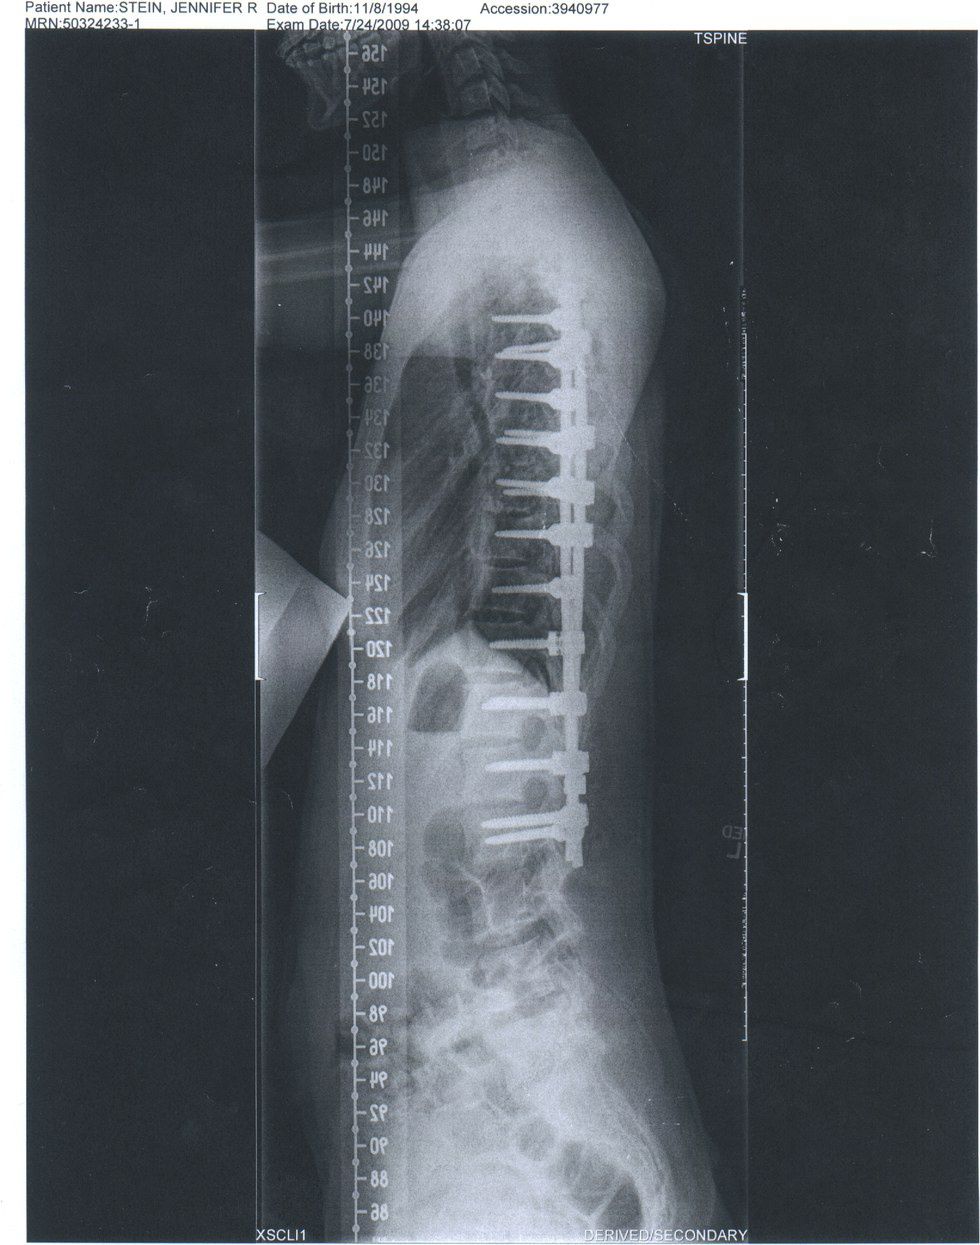

The scoliosis was painful, my body didn't function the way it used to. My muscles always ached and my ribs stabbing my lungs. I knew I wanted to have the surgery, and I decided right there that I wanted the surgery as soon as possible so I could play sport by my senior year of high school. The surgery consists of attaching titanium rods to my spine with surgical screws.

It all happened so fast. The pain in the fall, the diagnosis in the winter, and by spring I had my operation physical, I had blood drawn for the dialysis machine I would be hooked up to to keep my blood running during my surgery, and my last x-rays before the surgery. My curvature had increased to 55 degrees. In less than a year I had never heard of scoliosis and then I was having a incredibly risky surgery.

My time in the hospital was interesting. There was a lot of not sleeping that occurred, as I was checked on my a nurse every two hours. They needed to make sure I had enough meds, and to make sure I could still feel all of my limbs. The night the day after my surgery, I was whisked away to have a CAT scan, and the news we got back from the doctors was not good. They had put three of the screws in my lower vertebrae not the correct angle. I needed to have a second surgery. So on the 17th of July, I remember they disconnected me from my morphine drip and knocked me out for a second five hour surgery.

[Note: the "ooops" written in by the doctors]